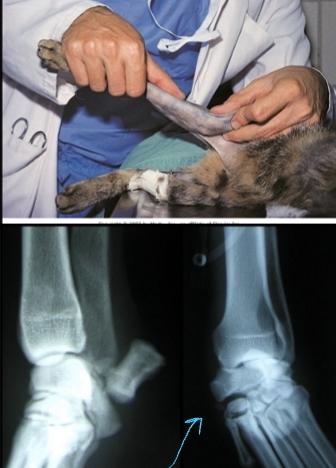

Patellar Luxation Pathophysiology

Et: Traumatic, Congenital

Shallow trochlear groove, malalignment of extensor mechanism, abnormal hip joint conformation, femoral malformation, tibial malformation, quadriceps tightness

Sig: Medial most common, 98%

Medial: Small breeds, young age

Lateral: large breeds

Grading Medial Patellar Luxation

Grade 1:

Patella can be luxated but returns to normal position spontaneously

Functionally normal

Grade 2:

Patella luxates out of groove occasionally

Can be replaced manually or reduces spontaneously

Grade 3:

Patella luxates most of the time

Can be replaced manually

Grade 4:

Patella luxates all of the time

Cannot be replaced back into the groove

Requires corrective osteotomy!!!

Patellar Luxation Diagnosis

Cs: Skipping, kicks leg straight backwards, non-weight-bearing lameness

Attempt to elicit luxation: Fully extend stifle joint, Internally rotate tibia, Apply medially directed pressure to patella while flexing stifle

Evaluate for CrCL tear: 15–20% of chronic MPL patients have CrCL tear

Radiographs: Stifle, pelvis, angular limb deformity, OA

Patellar Luxation Treatment

Rx: OA management, rest 8 weeks, Modified Robert Jones bandage 2 weeks

Sx: Only when CS and patient is effected!

Soft tissue: Medial retinacular release, Lateral retinacular imbrication

Bone: Tibial crest transposition(laterally), recession trochleoplasty(deepens groove), femoral/tibial osteotomies, anti-rotational suture, lateral stabilization, patellofabellar suture

Px: OA progress slowly, Half reluxate postop

Good: Grades 1-3

Poor/guarded: Grade 4